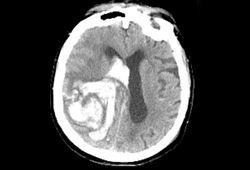

AVC hemorrágico

Hemorragia intracraniana à tomografia computadorizada (TC)

Arquivos de casos pessoais do Massachusetts General Hospital; usados com permissão